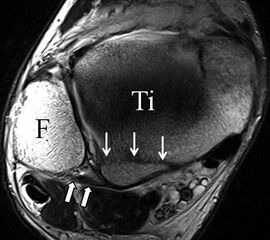

b. T2 fs axial. Infraktion des hinteren Volkmann‘schen Dreiecks (schmale, weiße Pfeile). Hier inserierende, intakte, hintere Syndesmose (breite, weiße Pfeile).

Abbildung 18b

Das Ligamentum tibiofibulare posterius (hintere Syndesmose) verläuft flacher und geht nach kranial in das Ligamentum tibiofibulare interosseus und nach kaudal in das Ligamentum intermalleolare posterius über. Letzteres bildet ein artikuläres Labrum zwischen Trochlea und Talus 9.

Da also die hintere Syndesmose an der posterioren Tibia inseriert, entspricht eine Fraktur oder Infraktion des hinteren Volkmann`schen Dreiecks funktionell einem knöchernen Ausriss des Ligamentum tibiofibulare posterius (Abb. 18 a und b). Aufgrund der Koinzidenz von Syndesmosenläsionen mit Innenbandverletzungen ist bei der Beurteilung gesondert auf solche zu achten.